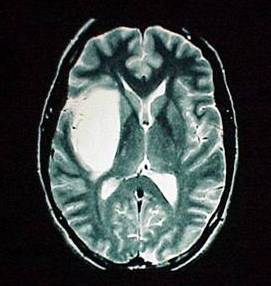

CU Neurosurgery Adult Brain Tumor Program

Adult Brain Tumor Main PageThe Brain Tumor Program at University of Colorado Hospital cares for the largest number of patients with brain tumors in the state of Colorado.  At UCH, we take a team-based approach to care, involving neurosurgeons, neuro-oncologists, neuropathologists, radiation oncologists, neuropsychologists, neuro-intensivists, research coordinators, and a brain tumor support group to enhance the physical and emotional wellbeing of patients diagnosed with brain tumors.  Specifically, we offer: